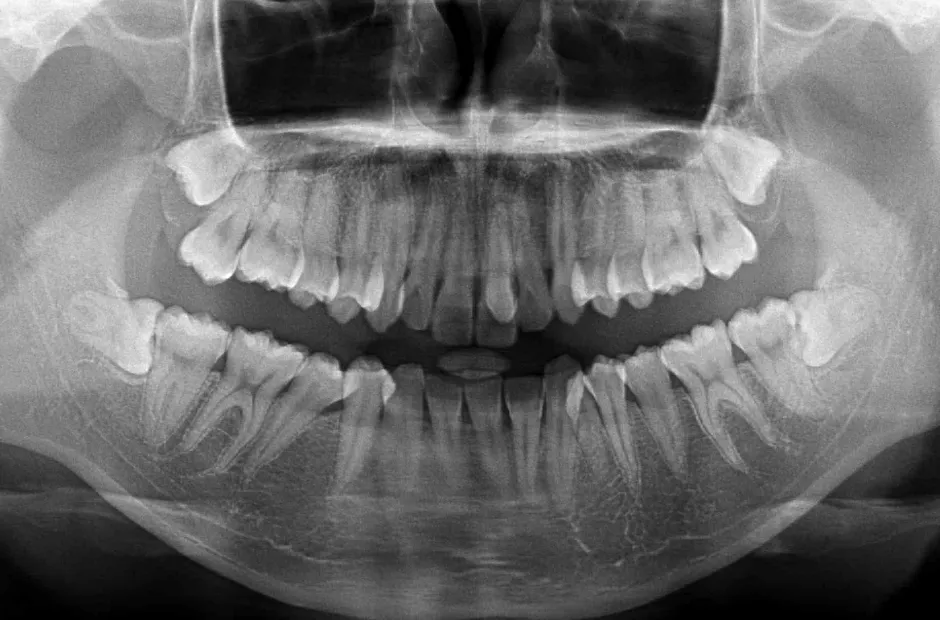

叢生

| 診断名・主訴 | 叢生 |

|---|---|

| 年齢・性別 | 43歳・女性 |

| 治療期間・回数 | 2年7か月 27回 |

| 治療に用いた主な装置 | 舌側矯正 |

| 抜歯部位 | 両顎4,4 |

| 治療費 | 100万円(税抜) |

| リスク・副作用 | 装置による違和感・疼痛・歯肉退縮・歯根吸収・虫歯のリスクなど |